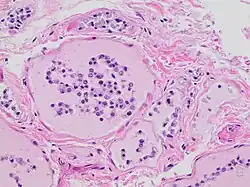

Lysosomes are membrane-bound organelles that typically contain a broad spectrum of enzymes capable of hydrolytic deconstruction of polysaccharides, proteins, nucleic acids, lipids, phosphoric acyl esters, and sulfates. This process requires compartmentalization and segregation of enzymes and substrates via a single intracellular membrane that prevents unwarranted destruction of other intracellular components. Under normal conditions, the molecular machinery of the cell is further protected from lysosomal enzyme activity by regulation of cytosolic pH. The activity of lysosomal hydrolases is optimal at a moderately acidic pH of 5, which is significantly more acidic than the more basic average pH of 7.2 in the surrounding cytosol.[1] However, the accumulation of products of glycolysis decreases the pH of the cell, reducing this protective effect. Furthermore, lysosomal membranes damaged by water retention in the cell will release lysosomal enzymes into the cytosol. These enzymes are likely to be active due to the decreased cytosolic pH and are thus free to utilize cellular components as substrates.[1]